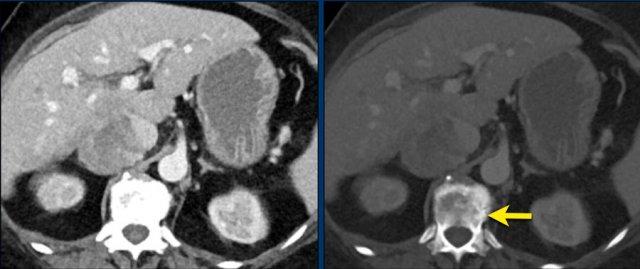

CT thì tĩnh mạch mặt cắt ngang này cho thấy một khối tuyến thượng thận phải kích thước rất lớn, nghi ngờ ác tính dựa trên kích thước lớn và tính không đồng nhất.

Tổn thương này là ung thư biểu mô vỏ thượng thận, nhưng trái với ví dụ trước, PET-CT FDG thực hiện tiếp theo cho mục đích phân giai đoạn chỉ cho thấy sự hấp thu nhẹ và chỉ ở phần ngấm thuốc mạnh nhất của khối u.

Hầu hết các ung thư biểu mô vỏ thượng thận đều có sự hấp thu FDG mạnh.

Sự thiếu hụt hấp thu FDG này có thể do khối u độ thấp với tốc độ phân bào thấp hơn hoặc có các thành phần xuất huyết hay hoại tử lớn.

CT thì tĩnh mạch mặt cắt ngang đầu tiên sau phẫu thuật, thực hiện 3 tháng sau khi cắt tuyến thượng thận trái vì ung thư biểu mô vỏ thượng thận kích thước lớn, cho thấy một nốt ngấm thuốc ở phía sau thận trái.

PET-CT FDG tái phân giai đoạn cho thấy sự hấp thu mạnh chỉ tại tổn thương này, được xác nhận là ổ di căn trên hình ảnh theo dõi tiếp theo.

Khối máu tụ dưới bao thận trái là không liên quan.